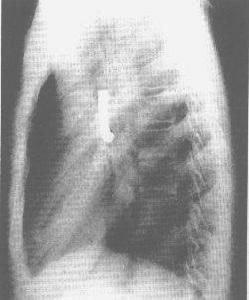

氣管、支氣管異物2.支氣管異物直接證象:不透X線的金屬異物在透視或照片中,可直接顯示異物的位置、形狀和大小。間接徵象:透X線及不透X線異物均可產生如下間接徵象:

(3)肺不張:為異物完全阻塞支氣管所致,表現為一側肺或某個肺葉、肺段的密度增高及體積縮小。

(4)肺部感染:異物停留時間較長時,相應肺葉可繼發出現肺炎,表現為密度不均勻的片絮狀模糊影像,也可以形成肺膿腫,出現空洞和液平面。